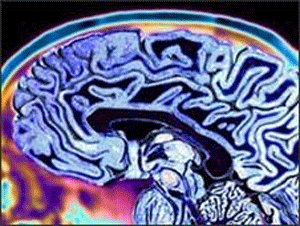

Al Zaimer K Ilaj K Liay Nai Tehqeeq